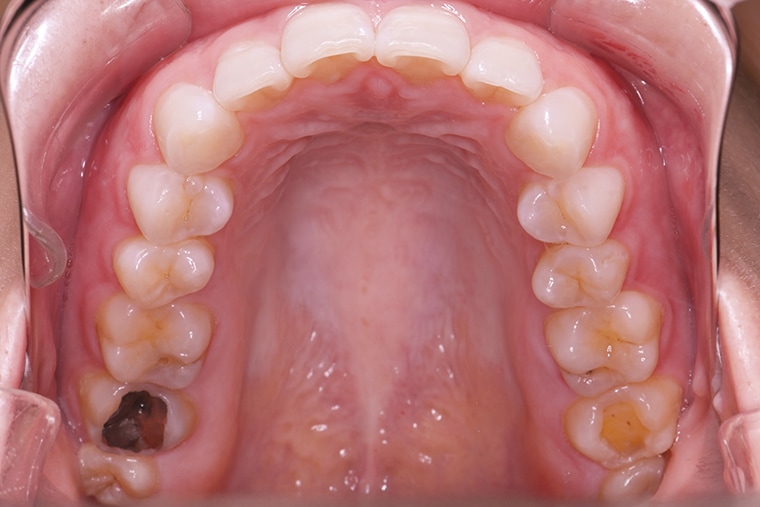

BEFORE